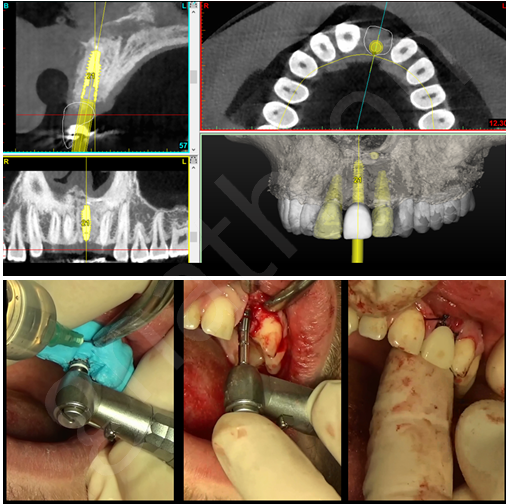

Έτσι έγινε και μετά από 6 μήνες και με βάση την ακριβή αντιστοίχιση των προεγχειρητικών θέσεων σε νέα υπολογιστική τομογραφία(CBCT) παρατηρήθηκε ικανοποιητική ανάπλαση για τοποθέτηση εμφυτεύματος. Ακολούθησε υπολογιστικό σχέδιο θεραπείας για καθοδηγούμενη τοποθέτηση του εμφυτεύματος (Εκόνα 2).